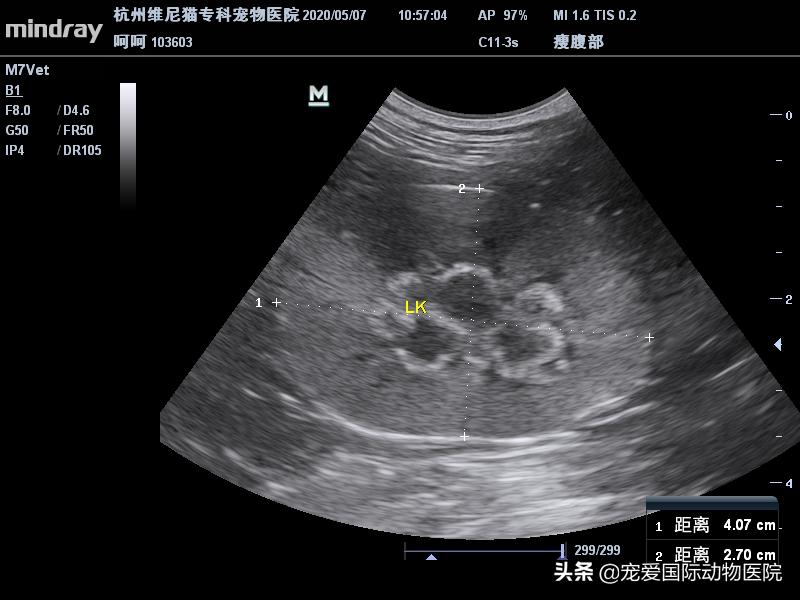

B超检测,见右侧肾盂扩张

内有一直径6MM结石